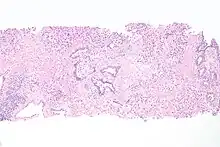

Cancer can also develop in the lining of the urethra.[19] When cancer is present, the most common symptom in an affected person is blood in the urine; a physical medical examination may be otherwise normal, except in late disease.[19] Cancer of the urethra is most often due to cancer of the cells lining the urethra, called transitional cell carcinoma, although it can more rarely occur as a squamous cell carcinoma if the type of cells lining the urethra have changed, such as due to a chronic schistosomiasis infection.[19] Investigations performed usually include collecting a sample of urine for an inspection for malignant cells under a microscope, called cytology, as well as examination with a flexible camera through the urethra, called urethroscopy. If a malignancy is found, a biopsy will be taken, and a CT scan will be performed of other body parts (a CT scan of the chest, abdomen and pelvis) to look for additional metastatic lesions.[19] After the cancer is staged, treatment may involve chemotherapy.